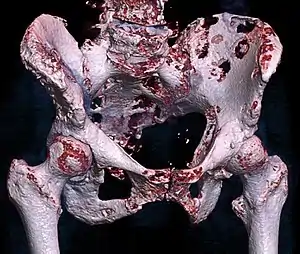

| 3D rendered CT scan of bone metastases of the hip bone, in a 60 year old woman with parotid gland cancer. Large lesions are seen on the ilium on the more distant side. Involvement of the vertebral column has caused a compression fracture. | |